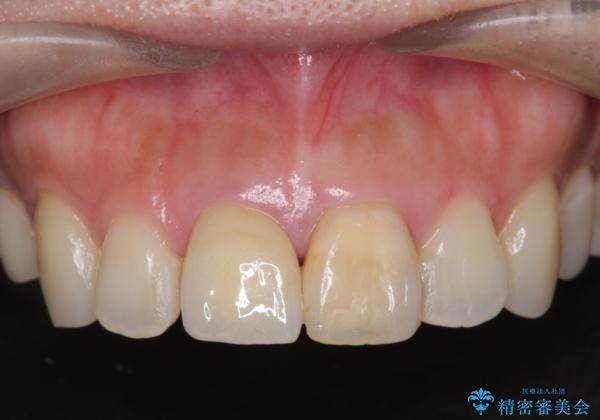

リアルな歯の色調にこだわるオールセラミッククラウン治療

- 歯の神経を除去したのちの、変色の改善を希望され来院されました。

再度根管治療を行ったのちの、オールセラミッククラン治療を計画します。

色調の再現に優れるオールセラミッククラウン スペシャルプランでの治療を希望されました。(保証5年間)

天然歯を再現したリアルな仕上がりに満足いただくことができました。

オールセラミッククラウン スペシャルプランは細やかな色調の再現に優れ、目立つ前歯の審美的な仕上がりがより達成されやすいプランです。